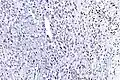

Tissue biopsy is the diagnostic modality of choice. Due to a high incidence of lymph node involvement, a sentinel lymph node biopsy may be performed. A common characteristic of epithelioid sarcoma (observed in 80% of all cases) is the loss of function of the SMARCB1 gene (whose protein product is termed BAF47, INI1, or hSNF5). Immunohistochemical staining of INI1 is available and helps to diagnose of epithelioid sarcoma. MRI is the diagnostic modality of choice for imaging prior to biopsy and pathologic diagnosis for most patients.

High mag. (SMARCB1)